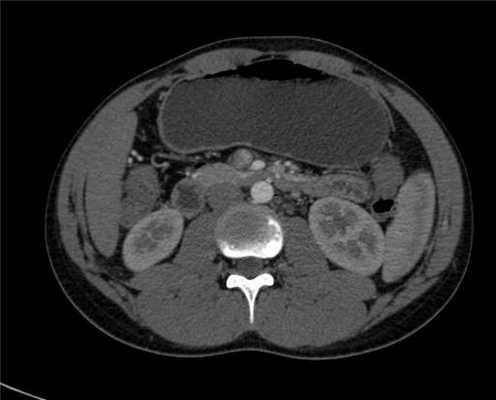

Анамнез: Юноша, 17 лет. жалобы на боли в области пупка и супра-умбиликальной области, после еды (post-prandial). В анманезе были эпизоды рвоты после обильного застолья.

Описание исследования Орально дали "серый", или его еще называют "отрицательный" контраст - обыкновенную воду, так лучще видно слизистую. На представленных вашему вниманию сканах, мы можем определить довольно интересную патологию. Синдром верхней брыжеечной артерии (синдром васкулярных ножниц), при котором происходит сдавление 3-го сегмента 12-ти перстной кишки между брюшной аортой и ВБА. Обратите внимание, у пациента ВБА (верхняя брыжеечная артерия) отходит от аорты под очень острым углом в 14-15 градусов (норма 34-68), расстояние между аортой и ВБА на уровне прохождения 3-го сегмента 12-ти перстной кишки около 6-7 мм (норма 13-34 мм), такие цифры являются однозначными ктритериями подтверждающими диагноз синдрома ВБА.